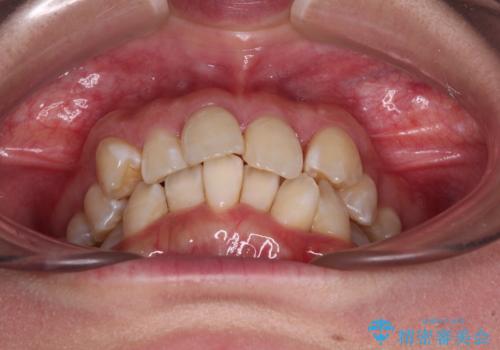

- 前歯1本が後ろ側に隠れてしまうほどのデコボコを気にして来院された患者様です。

前歯のデコボコが顕著なのはもちろんですが、左右ともに奥歯の咬み合わせに問題があり、上顎臼歯が前方位にある状態でした。

上顎は左右の第一小臼歯2本を、下顎は左右第二小臼歯2本を抜歯することで、奥歯の咬み合わせを改善しながら、デコボコを解消していくこととしました。